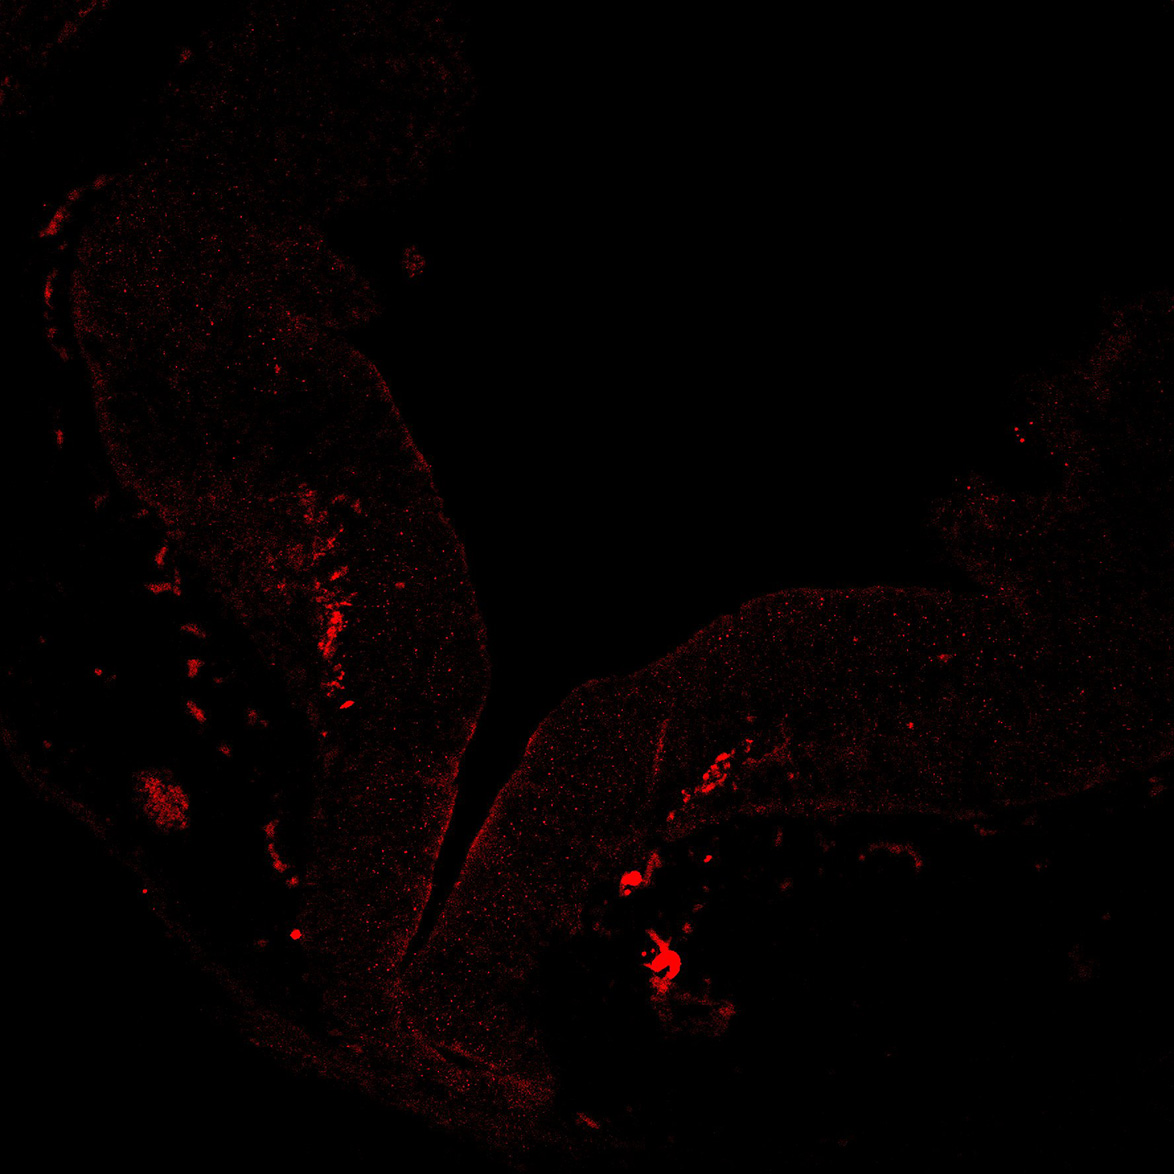

An anatomical analysis of the developing human midbrain from 6 post-conceptional weeks (PCW) to 22 PCW reveals increased tissue complexity, characterized by the emergence of dopaminergic nuclei, as highlighted by immunofluorescence analysis for tyrosine hydroxylase (TH).

11PCW

DAPI

11PCW human midbrain

MAP2

SOX2

Merged

TH